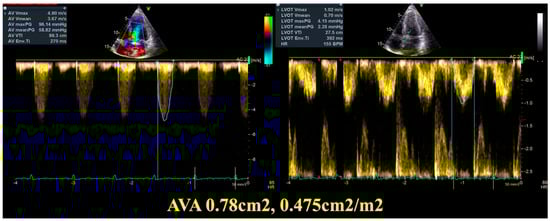

| Gestational Age (Weeks) | Heart Rate (bpm) | Hb (g/dL) | NT-proBNP (pg/mL) | 6mWT (m) | LVEF (%) | LVOT VTI (cm) | AV VTI (cm) | Maximum AV Gradient (mmHg) | Mean AV Gradient (mmHg) | Indexed Aortic Valve Area (cm2/m2) |

|---|---|---|---|---|---|---|---|---|---|---|

| 22 | 76 | 11.5 | 45 | 670 | 59 | 27.5 | 99.3 | 96 | 58 | 0.475 |

| 3 months postpartum | 70 | 11.9 | 54 | 654 | 60 | 28.3 | 118 | 103 | 68 | 0.50 |